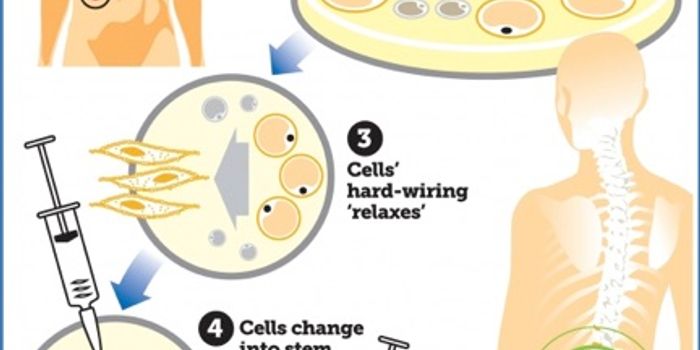

APR 06, 2016Clinical & Molecular DXBetter learn to embrace your fat cells, because scientists have found unprecedented, awesome new uses for these cells. U ...

APR 02, 2016Clinical & Molecular DXJust in the past few months, biomedical engineers have created lab-grown heart cells, retinal nerve cells, and even voca ...

SEP 19, 2016Clinical & Molecular DXIn the past year, biomedical engineers have created lab-grown heart cells, retinal nerve cells, and even vocal cords tha ...